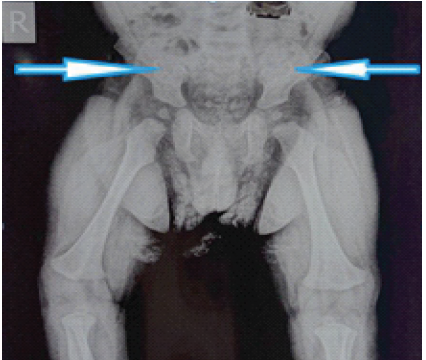

Methicillin-Resistant Staphylococcus aureus Iliac Osteomyelitis with Cortical Breach Mimicking Septic Arthritis of the Hip in a Child: A Diagnostic Pitfall

Devender Kasotya , Ranjeet Choudhary , Ramesh Negi , Gaurav Kumar Sharma , Umesh Kumar Bahagotia , Anirudh Dwajan ………………………………p.188-193